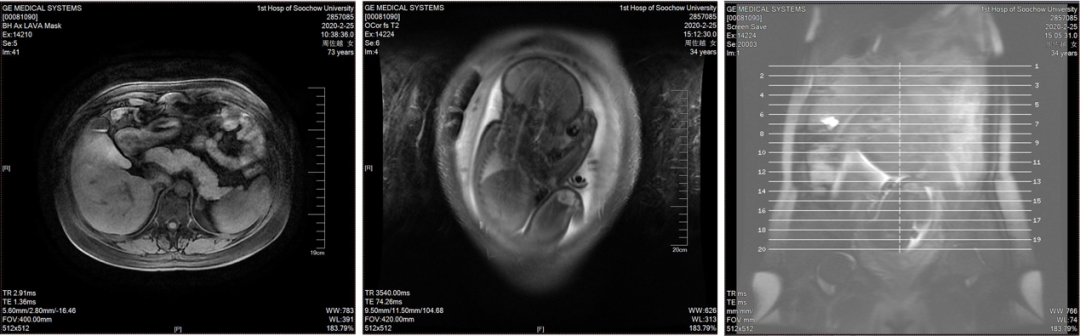

【现病史】 【既往史】 【婚育史】 【月经史】 【家族史】 直系亲属无类似疾病史。父亲高血压病史,否认其他家族遗传性疾病史。 【入院后的检查检验】 ✦经腹部+阴道联合超声(2017-02-15,我院): ✦肿瘤指标: 【入院诊断】 2、子宫颈炎 3、不孕症 中青年女性,已婚未育,因“B超发现盆腔包块半年余”就诊。患者右侧附件区可见一个混合回声,形态不规则,边界尚清晰,内部回声不均匀,大小约98mm*70mm*64mm,其内可见不规则液性回声,附壁可见低回声突起,大小约38mm*15mm*39mm,其内可见点状彩色血流信号可见彩色血流信号。患者既往有卵巢囊肿切除术史。肿瘤指标糖类抗原CA125:755.5U/mL,人附睾蛋白4:124.9pmol/L。 经腹双侧卵巢肿瘤剥除术+大网膜切除+阑尾切除术+腹主动脉旁淋巴结取样术+盆腹腔多点腹膜活检术+盆腹腔转移肿瘤结节切除术 【术中探查见】 【术中快速病理】 【术后常规病理】 【术后基因检测结果】 【术后诊断】 2、卵巢交界性浆液性乳头状瘤Ⅲc期 3、右侧卵巢巧囊术后 4、腹主动脉旁淋巴结内异症 【术后治疗】 TC化疗6L疗程。化疗期间予诺雷德3.6mg皮下注射。 【术后妊娠】 ✦产科病史: 入院检查:宫高:34cm,腹围:104cm,估计胎儿大小:3500g,胎方位RSA,FHR:144次/分,先露:臀。 辅助检查:B超示:双顶径:93mm,腹周径:307mm,股骨长:68mm,羊水指数:89mm,胎盘附着于子宫后壁,Ⅲ-级,考虑胎儿脐带绕颈一周可能,LSA位。 ✦肿瘤指标: ✦MRI(2020-02-25,我院): ✦手术方案: 于2020-02-26在全麻下行子宫下段剖宫产术+次广泛性子宫切除术+双侧附件切除术+盆腔淋巴结清扫术+腹主动脉旁淋巴结清扫术(肾静脉水平)+盆腹腔转移肿瘤结节切除术+盆腹腔多点腹膜活检术+部分网膜切除术 ✦分娩记录: 手托臀娩出一女婴,体重2850克,评分10-10分 ✦术中快速: (左卵巢)交界性浆液性乳头状囊腺瘤,部分呈微乳头型,伴上皮内癌,待常规多取材除外有无浸润。 ✦术后常规: 患者术后每隔半年规律复查至今,复查内容包括肿瘤指标(CA125、CA199、HE4)、生化全套检验及B超检查,均未见明显异常。 延展讨论 1、手术方案的选择 卵巢交界性肿瘤相对于卵巢肿瘤而言恶性程度较低,复发率低且复发较晚,患者生存期延长,死亡率较低。近年来女性卵巢交界性肿瘤的发病年龄趋于年轻化。在临床调研中显示有50%的患者确诊时<40岁。由于BOTs患者多为育龄期女性,对生育功能的保留是治疗过程中应重点考虑的因素之一。目前保留生育功能手术术式有单侧肿瘤剔除术、单侧附件切除术、双侧肿瘤剔除术(BOC)和单侧附件切除术+对侧肿瘤剔除术(UAC),分期不是绝对禁忌证。此外,BOT易复发,常见高危因素有FIGO分期、手术方式和组织学类型等。浆液型、晚期、微乳头和双侧肿瘤与高复发率相关;单侧附件切除术预后总体优于肿瘤剔除类手术。对于强烈要求保留生育功能的患者需要充分评估肿瘤特性、做好术前告知,谨慎选择术式,术后规律随访。 由于卵巢交界性肿瘤一般分化良好,其代谢活性近似于良性肿瘤,缺乏对化疗药物的敏感性或耐药性,故对于早期患者和术后无残留病灶的患者不建议立即进行辅助性化疗,而应积极定期随访。 2、术后辅助生殖技术 研究表明卵巢交界性肿瘤实行保留生育功能手术对后续不孕症行体外受精、胚胎移植的妊娠结局无显著不良影响。BOTs患者实施辅助生殖技术(assisted reproductive technology,ART)的时机十分重要,大部分观点认为应当在术后至少1-2年再尝试ART但考虑到ART治疗的间隔时间过长可能对于女性卵巢储备功能有较高的要求,术后的妊娠应当在评估了肿瘤复发风险和预后的情况下尽快进行,在术后半年至1年内尝试妊娠。而对于术前术后检测卵巢功能出现下降,无或低自然受孕机会的患者应缩短ART的时间间隔。对于术后病理提示肿瘤有微乳头或间质浸润等情况者,应尽早或在术后半年至一年内开始尝试妊娠。 3、妊娠时机的选择 本案例中患者于化疗结束后半年开始积极备孕,行IVF失败后自然受孕,并于腹腔镜双侧卵巢肿瘤剥除术后2年妊娠。对于有生育需求的患者,妊娠时机的选择也十分重要,原则上应避开复发高峰期,可在术后6-12个月内尝试妊娠;术后选择化疗的患者应在停用化疗药物6-12个月后。还应继续关注其卵巢功能及激素水平,在孕早期及时补充黄体酮保胎,以期达到良好的妊娠预后。

孕中:中下腹腔胎儿影;肝II段异常信号影,考虑FNH可能大,建议随访复查;肝右叶小囊肿;右肾小囊肿;左肾上腺内支皮质增生可能。